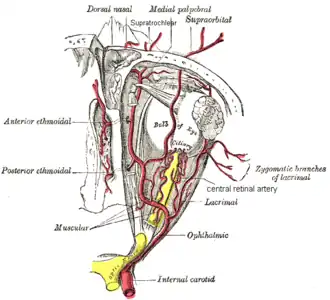

The ophthalmic artery and its branches. (Central retinal artery visible at center.) | |

The central retinal artery (retinal artery) branches off the ophthalmic artery, running inferior to the optic nerve within its dural sheath to the eyeball.

The central retinal artery supplies blood to all the nerve fibers that form the optic nerve, which carries the visual information to the lateral geniculate nucleus of the thalamus, including those that reach over the fovea. Its blood flow can be revealed by fluorescein angiography or laser Doppler imaging.[4]